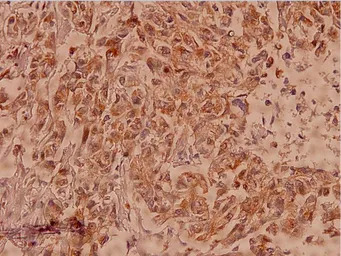

IHC-P analysis of human breast carcinoma tissue using GTX66616 Claudin 7 antibody.

Dilution : 1:100